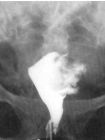

子宮上部較寬,稱子宮體,其上端隆突部分,稱子宮底。子宮底兩側為子宮角,與輸卵管相通。子宮的下部較窄,呈圓柱狀,稱子宮頸。

子宮呈前後略扁的倒置梨形,重約50g,長7-8cm,寬4-5cm,厚2-3cm,容量約5ml。子宮上部較寬稱宮體,下部較窄呈圓柱狀稱宮頸。成年婦女宮體與宮頸長度比例為2:1如何預防子宮肌瘤